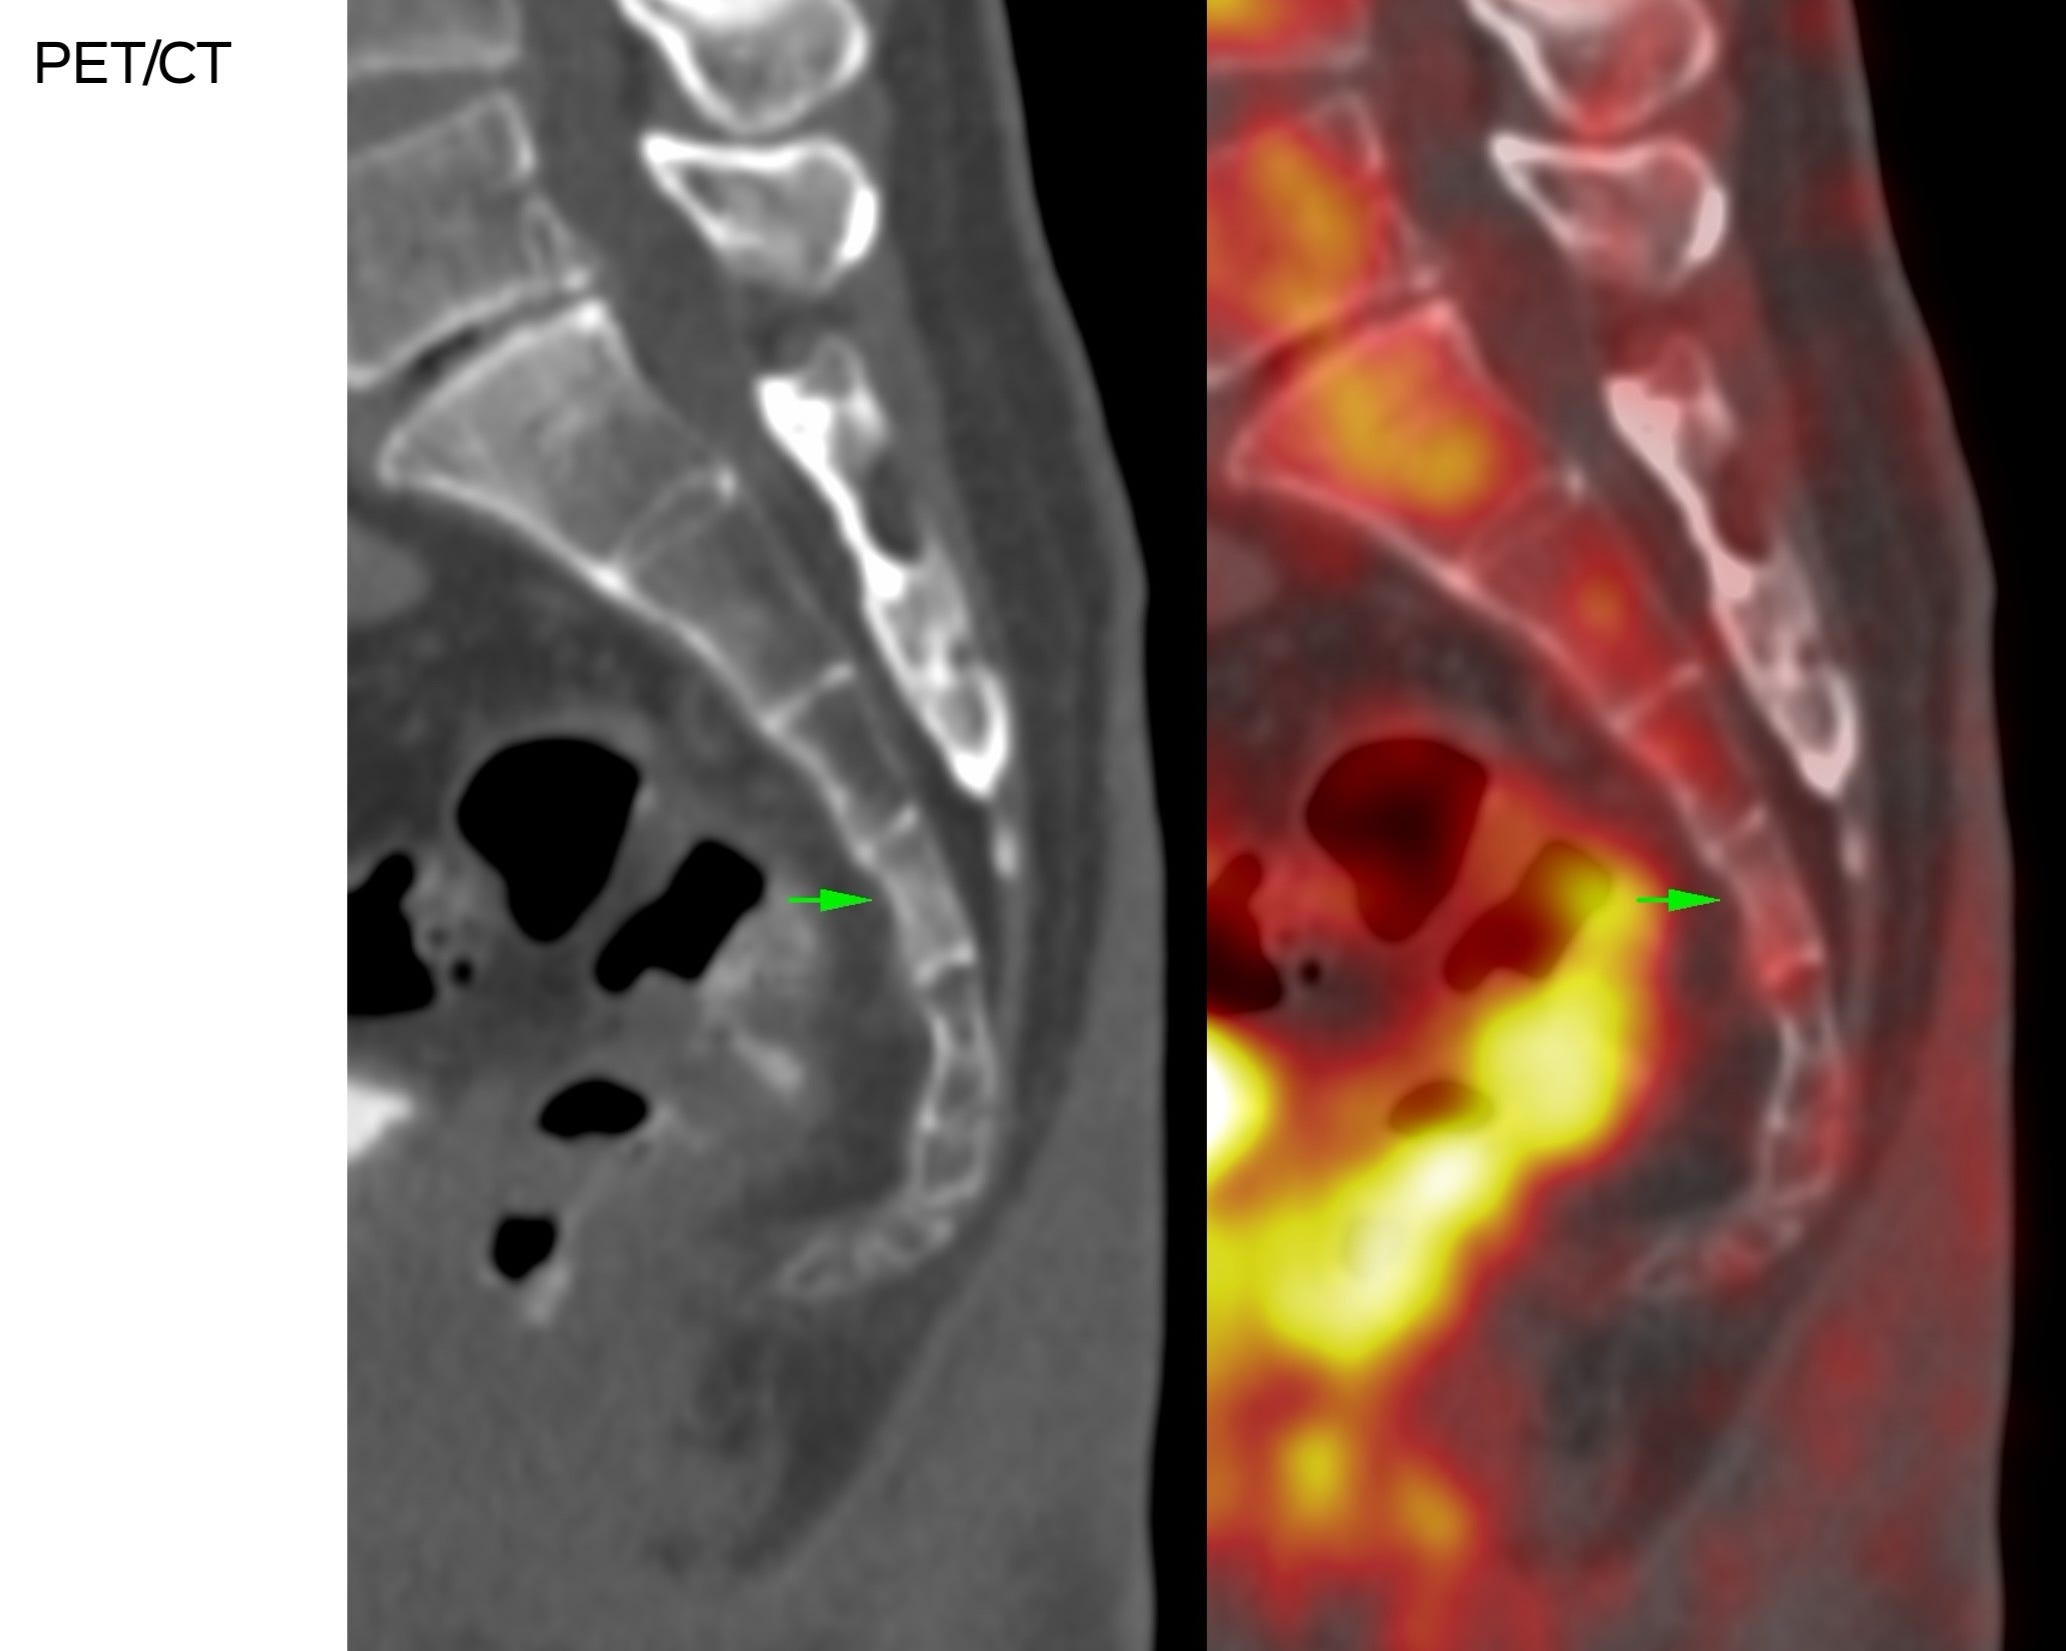

The patient’s symptoms and MRI did not match. A PET/CT was then done for further work-up.

What do you think is the diagnosis?